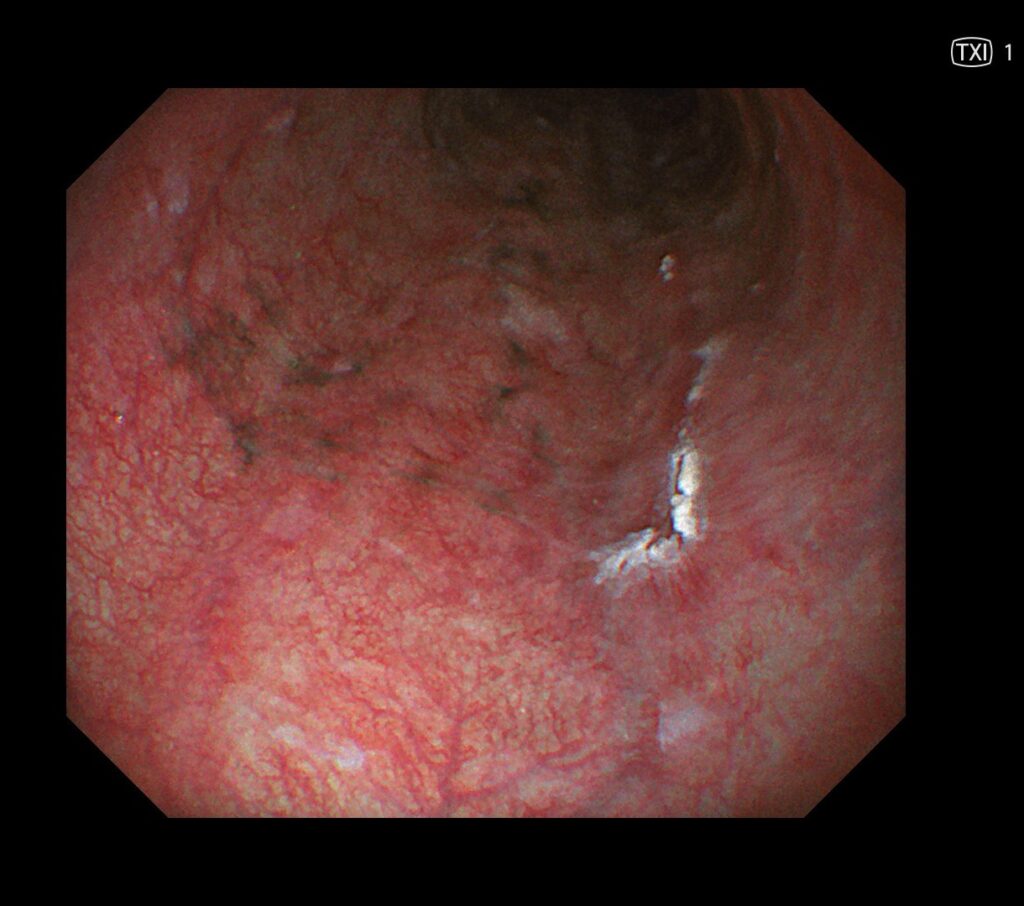

通常観察では周囲粘膜より、やや茶食の領域が散見されています。

この時点で、入念に食道癌の発見に集中します。

近傍に癌を疑う所見を認め、拡大観察可能な内視鏡に切り替え、再度観察。